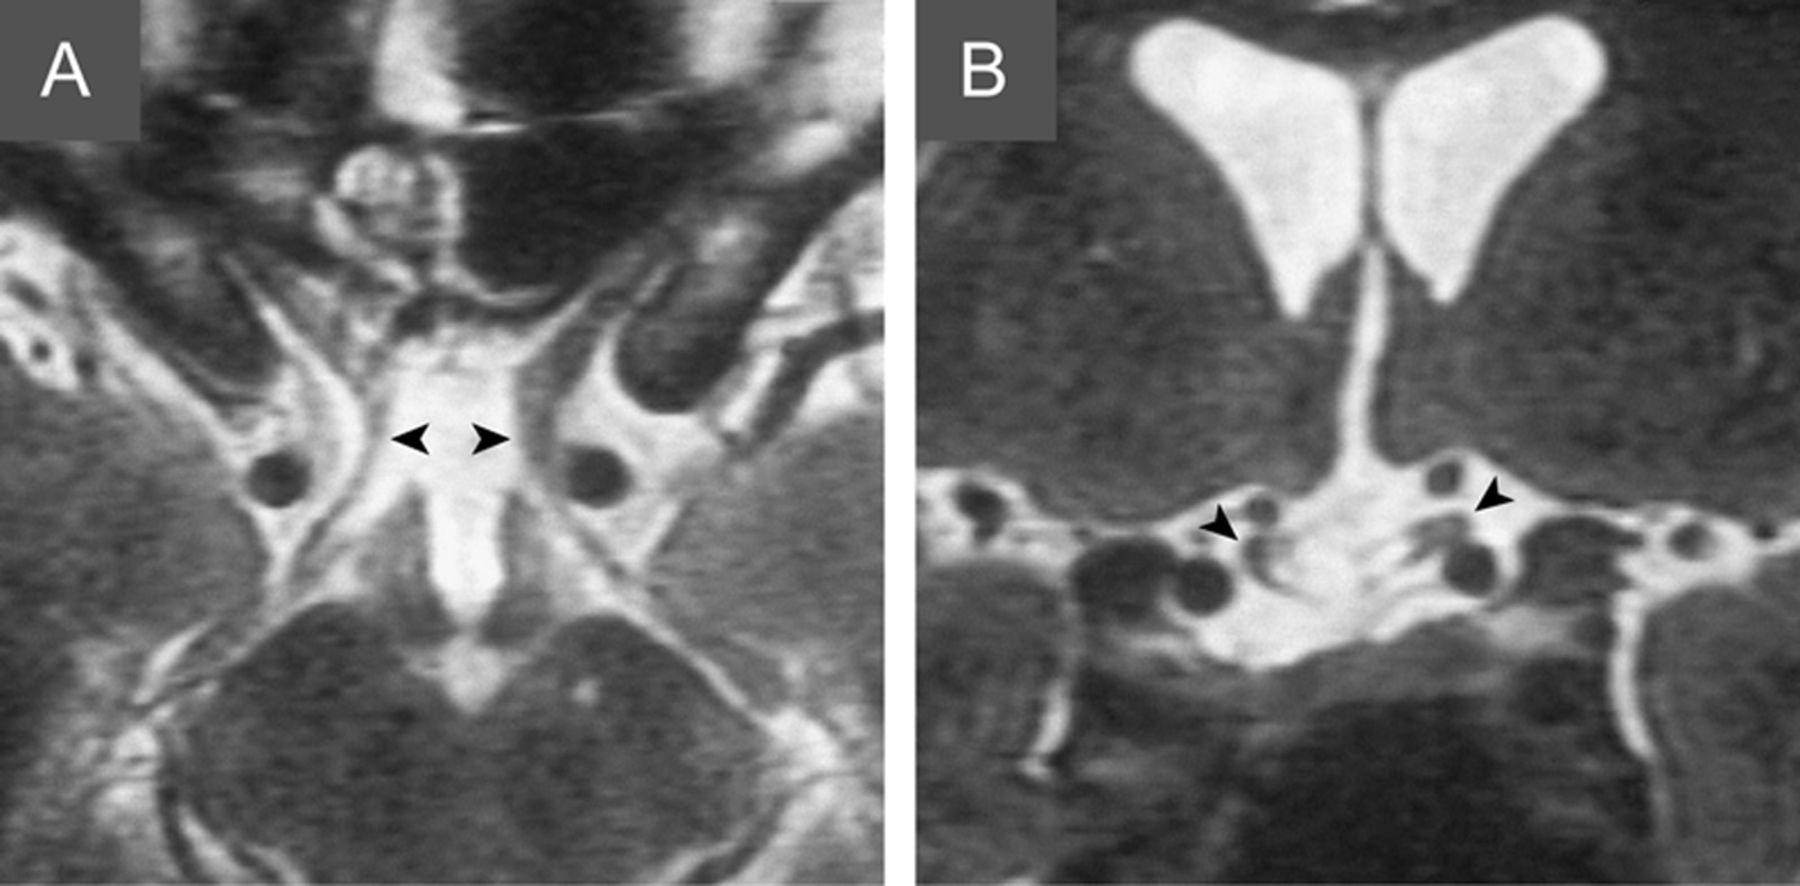

一个59岁的女人参观了眼科常规检查。自从与额叶损伤重型颅脑损伤在16岁,她经历过间歇性复视和困难找到错误的对象,但当过职员在她的生活。本篇充满只有轻微的外斜视,但视野测量显示完整的双时态偏盲(图1 A和C)。双时态偏盲是由干扰引起的视神经交叉的交叉神经纤维(图2),通常由于上质量,或很少,头部创伤后。1没有相应的视网膜区域,病人不再能够使两个障碍,失去了立体观测,通常开发斜视。收敛在一个附近的目标诱发postfixational失明的差距2鼻障碍(图1中,B和D),在更远处的物体消失。2这种不同寻常的视野缺陷解释病人的投诉。

图1

Postfixational失明由于创伤性视神经交叉的破裂

(C)标准视野测量显示完整的双时态偏盲。单眼视觉领域的右眼(蓝色)和左眼(红色)叠加。(B, D)视野测量在目标附近收敛在一个演示postfixational失明的差距2鼻障碍(黑色楔)。